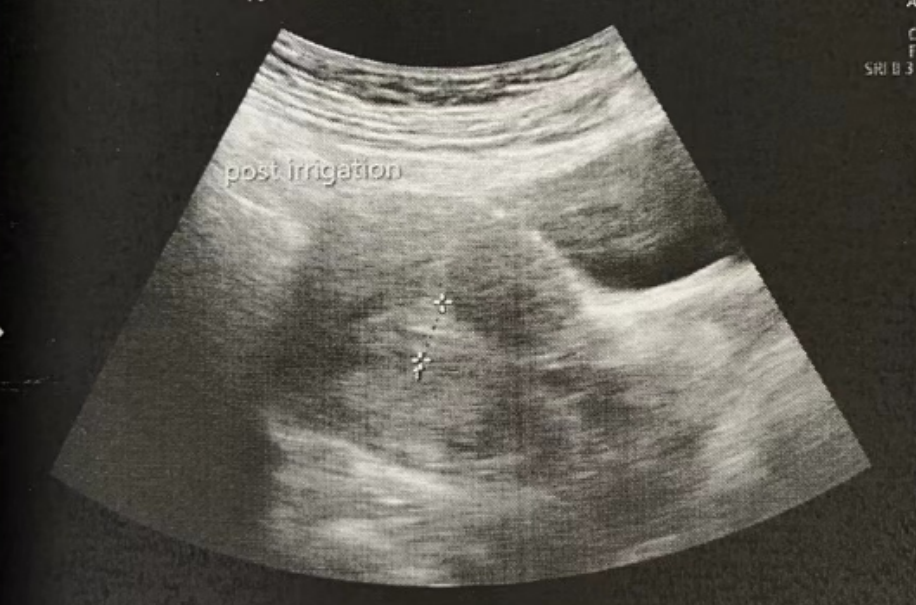

微创清积液

在进行3毫升的子宫峡部切口冲洗后,经过经腹超声检查显示子宫内膜呈三线状,且子宫腔内未见液体。

术后给予抗生素预防感染,为后续胚胎移植扫清子宫环境障碍。

• Pre-Irrigation灌洗前:

• Pre-Irrigation灌洗后: